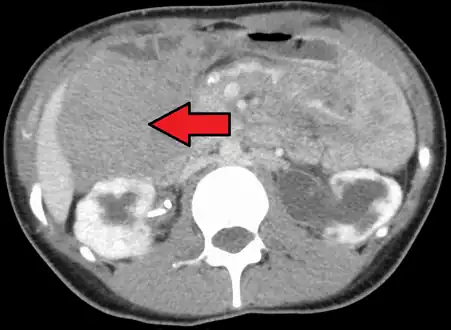

Desmoid tumor as seen on CT scan

Aggressive fibromatosis or desmoid tumor is a rare condition. Desmoid tumors arise from cells called fibroblasts, which are found throughout the body and provide structural support, protection to the vital organs, and play a critical role in wound healing. These tumors tend to occur in women in their thirties, but can occur in anyone at any age. They can be either relatively slow-growing or malignant. However, aggressive fibromatosis is locally aggressive and can cause life-threatening problems or even death when they compress vital organs such as intestines, kidneys, lungs, blood vessels, or nerves. Most cases are sporadic, but some are associated with familial adenomatous polyposis (FAP). Approximately 10% of individuals with Gardner's syndrome, a type of FAP with extracolonic features, have desmoid tumors.[1]